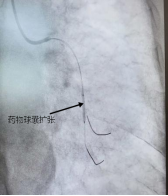

一位91岁高龄的老人,因四个多月来反复出现胸痛、心慌,最近一周症状再次加重,并伴有明显的食欲减退、吃不下饭,被送入pilipili 治疗。造影显示LCX(回旋支)远段狭窄90%,OM2开口及近段狭窄40%,随时有急性心梗的风险。李绍波主任运用IVUS(血管内超声)技术对病变血管进行检查,从传统“造影看轮廓”升级为“超声看结构”,清晰发现患者狭窄处病变以纤维斑块为主,且病变范围相对局限,符合药物球囊治疗指征。随后,李绍波主任为患者实施IVUS指导下的药物球囊治疗,术后患者血管恢复通畅,胸痛症状即刻缓解,同样无需植入支架。